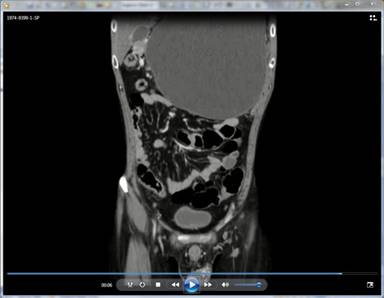

A chronic alcoholic 29-year-old male presented with complaints of heaviness in the scrotum since a few days and lumpish feel in the abdomen since a few weeks. Sonography scrotum revealed multiple dilated, tortuous serpiginous anechoic channels situated on the posterolateral aspect of the left testis (Image 1).These channels were venous in nature and had continuous reversal of flow on Valsalva maneuver. The right testis was normal. On abdominal sonography, there was a 20x12x18 cm huge cystic lesion present predominantly in the epigastrium and left hypochondrium. A CT was performed which confirmed the findings. Besides, there was dilation of the pancreatic duct with calcification in the pancreatic head. The cystic lesion was a huge pseudocyst in the setting of chronic calcific pancreatitis. The pseudocyst was seen to compress the left renal and testicular veins with consequent secondary varicocele on left. There was rightward displacement of the aorta (Image 2: a) and inferior vena cava (Image 2: I). CT in venous phase with coronal reconstruction depicts the huge pseudocyst centered predominantly in epigastrium and left hypochondrium. There is prominence of testicular venous plexus on left (Videoclip). The serum lipase and amylase levels were 501 U/L (reference range: 40-290 U/L) and 1,024 IU/L (reference range: 25-125 IU/L), respectively. A cystogastrostomy was performed which lead to decompression of both the pseudocyst and the varicocele.